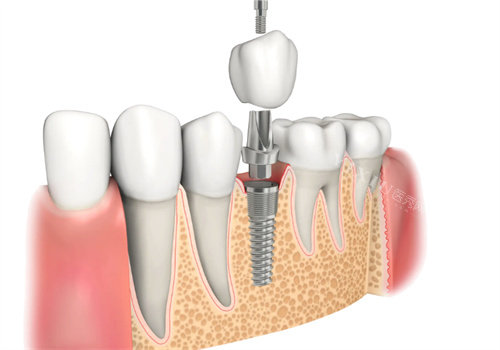

开封尉氏植卓口腔的医生团队是其赢得好口碑的关键因素。团队成员均毕业于正规口腔院校,拥有多年临床经验,在各自擅长领域深耕细作。以种植牙项目为例,负责种植牙的医生熟练掌握即刻种植、小创口种植等新型技术,面对复杂的缺牙情况,如多颗牙缺失、骨量不足等,也能凭借丰富经验与娴熟技术制定个性化方案。

在特色项目上,种植牙涵盖多种品牌种植体,从性价比高的国产植体到高端进口植体均有提供;牙齿矫正除了传统金属矫正,还有美观舒适的隐形矫正器可供选择;对于儿童口腔问题,也开设了儿童龋齿治疗、乳牙拔除、早期咬合诱导等项目,多角度呵护全年龄段人群的口腔健康。

众多患者的真实评价,是植卓口腔良好口碑的有力证明。一位做过种植牙的患者评价道:“原本担心种植牙手术很复杂,但是植卓口腔的医生特别正规,手术过程很顺利,现在种的牙用起来和真牙一样,真的很感谢!” 还有家长分享:“孩子在这里看牙一点都不抗拒,医生特别有耐心,会用有趣的方式引导孩子配合治疗,以后看牙就认准这里了。” 从这些评价中可以看出,开封尉氏植卓口腔凭借正规的技术、齐全的服务,赢得了患者的认可与信赖。